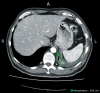

Management of malignant pleural mesothelioma (MPM) remains a clinical challenge and the incidence of the disease will continue to increase worldwide. Several aspects of mesothelioma treatment are discussed controversially, in particular, regarding extent and best type of surgery, radiotherapy, and the role of neoadjuvant or adjuvant treatment. However, best survival data is reported from groups using multimodality treatment including macroscopic complete resection (MCR) achieved by either extrapleural pneumonectomy (EPP) or (extended) pleurectomy/decortication for patients qualifying from the tumor biology, stage, and patient's performance status and comorbidities. Several aspects have to be considered during surgery but morbidity and mortality have been reduced at experienced centres. The final analysis of extended selection algorithms is pending.